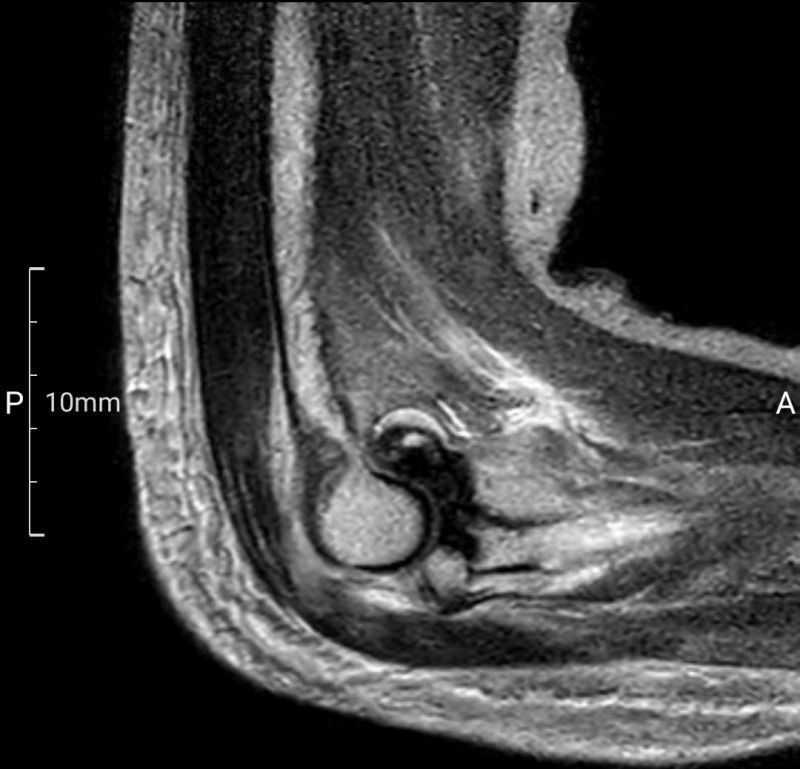

术前,南溪山医院3D打印中心利用高精度扫描技术获取患者肘关节的三维数据,并进行参数化分析,为患者量身定制了3D打印桡骨小头假体。这一假体不仅与患者骨骼高度匹配,还能在手术中即插即用,极大地缩短了手术时间,并确保了手术的精准性和安全性。

手术由张立主任及贵鹏医师团队共同完成。术中,医生们通过5厘米的切口暴露骨折部位,并依据术前规划精准处理骨折断端。随后,3D打印桡骨小头假体被顺利植入,实现了对桡骨头关节面的完美重建。术后,患者恢复顺利,基本功能得到有效恢复。